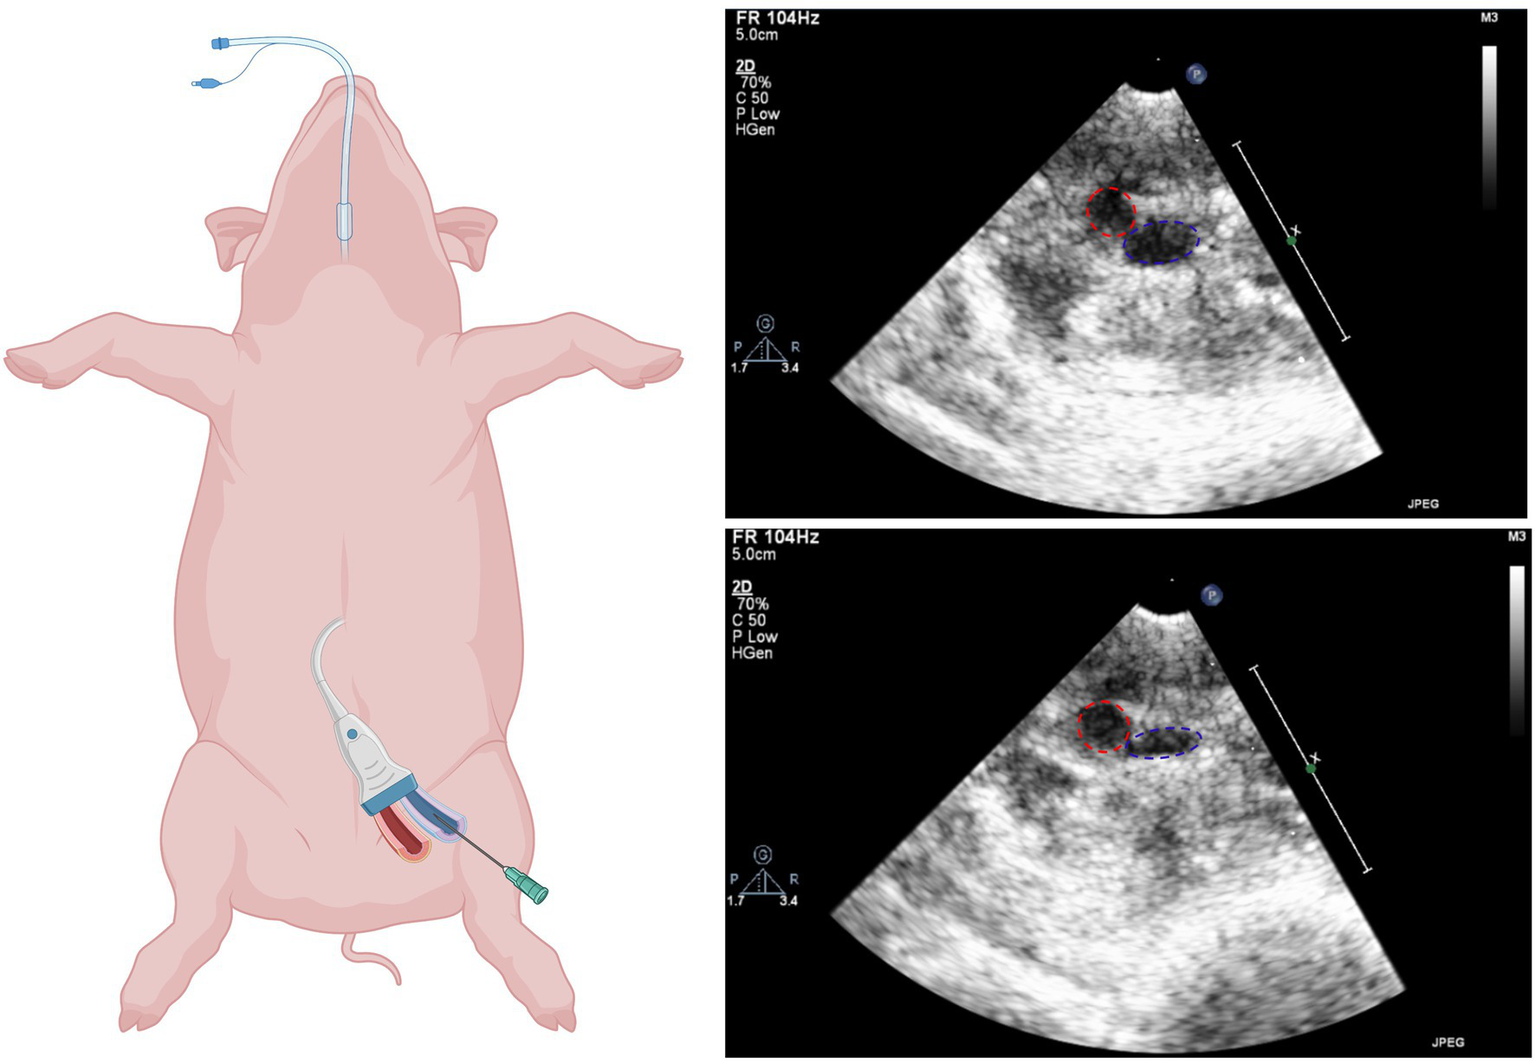

Ultrasound-guided groin access: The femoral artery and veins were located using ultrasound and tested for compressibility (veins completely compressible, arteries remain spheric). An angiographic needle (18 G, 70 mm, Cordis Cashel, County Tipperary, Ireland) was used to access the veins and to place an 8F sheath via a guidewire (Seldinger technique; Figure 1).

Figure 1

Ultrasound guided femoral access. Left: Schematic illustration of vascular access (biorender.com). Right: Ultrasound images of femoral artery (red) and femoral vein (blue) before (top) and after (bottom) compression.

Groin access

Uncomplicated ultrasound-guided femoral vein access could be achieved in all animals (Figure 1). No bleeding or inadvertent arterial punctures occurred.